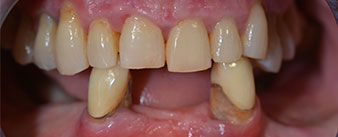

La paciente de 64 años se presentó con una dentición residual compuesta por las piezas dentales 38, 33 y 43 en el maxilar inferior y con una prótesis temporal fijada con ganchos en el maxilar inferior (figs. 1 y 2).

dentición residual

Fig. 1

Fig. 2

El tratamiento periodóntico necesario y la extracción de las piezas en el maxilar superior debía realizarse en un momento posterior, ya que la paciente es profesora y, en el momento de la consulta, estaba ocupada con los exámenes para las pruebas de acceso a la universidad. La paciente no podía comer ni hablar adecuadamente, ya que la prótesis temporal se rompía con mucha frecuencia y con una carga mínima.